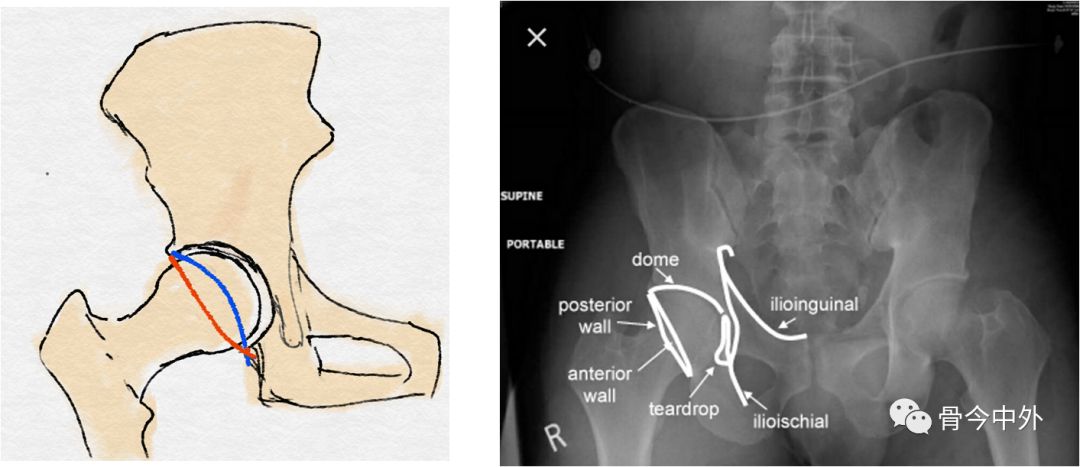

3、骨盆连续性的评估

髂耻线:

连接髂骨内缘与耻骨上缘的弧线

反映髋臼前柱、骨盆前环的完整性

髂坐线:

连接髂骨内缘与坐骨内缘的弧线

反映髋臼内壁、四边体的完整性

泪滴:

U型的弧线

代表了髋臼的内缘

前唇线:

髋臼前缘所连成的弧线(左图中蓝线)

反映髋臼前壁的完整性

后唇线:

髋臼后缘所连成的弧线(左图中红线)

反映髋臼后壁的完整性

8字征:

髋臼前缘与后缘交叉

提示髋臼撞击综合征